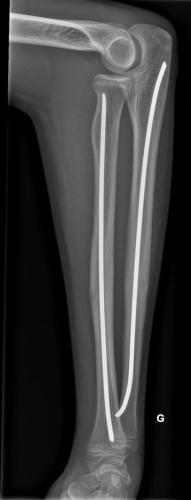

Fracture de l’avant-bras 31 mars 202519 mars 2024 par Damien Traitement Traitement orthopédique Embrochage centro-médullaire